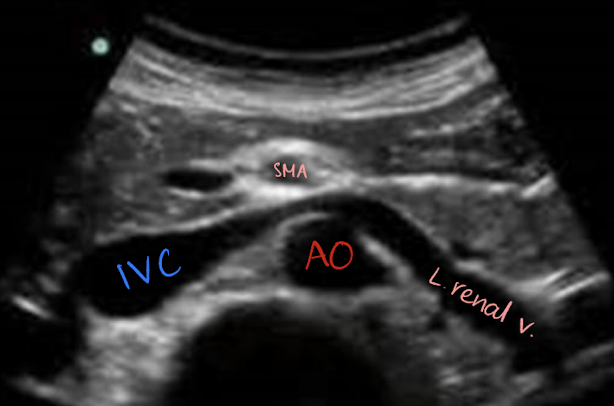

superior mesenteric artery (SMA)

2nd branch off AO

1 cm inferior to celiac trunk

follows anteroinferior course along AO and divides into several arteries

branches supply the small intestine, ascending colon, part of transverse colon, pancreatic head, and duodenal area

surrounded by echogenic fat (retroperitoneal fascia)

SONO in TRANS: circular structure posterior to pancreas and anterior to AO and left renal vein

renal veins (RRV and LRV)

posterior to SMA

anterior to AO

LRV is longer than RRV